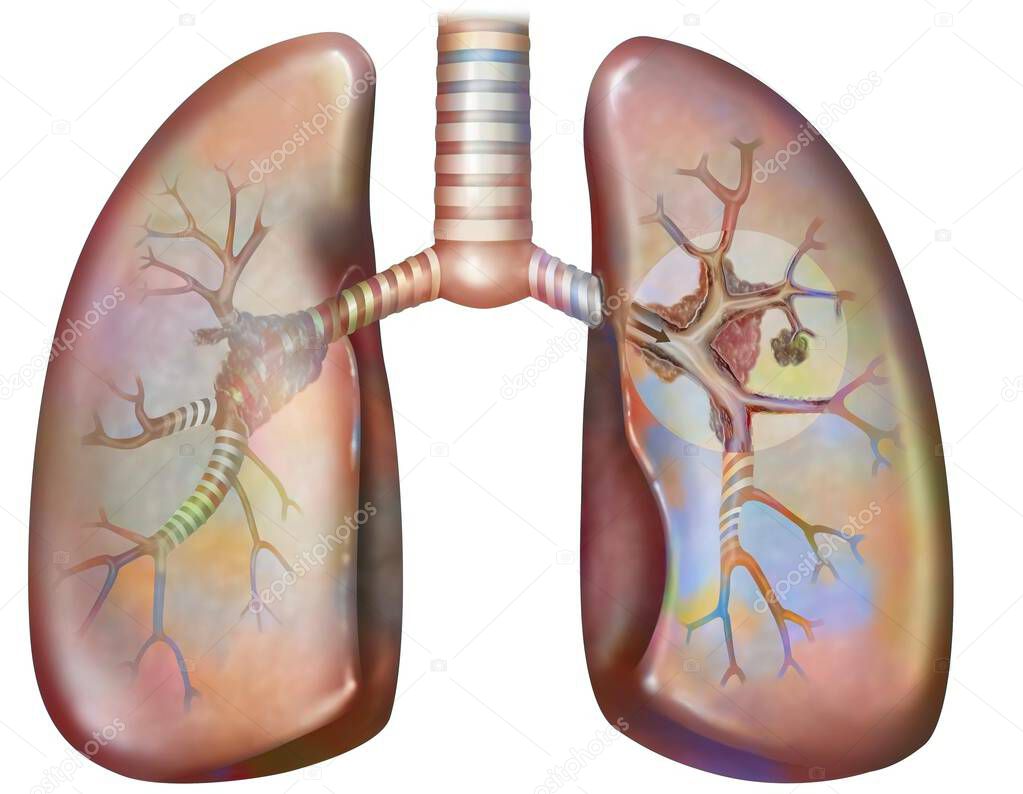

- Рак легких курильщика (с наличием депозитов смолы в бронхах).

Рак легких курильщика (с наличием депозитов смолы в бронхах).

Рак легких курильщика (с наличием депозитов смолы в бронхах).